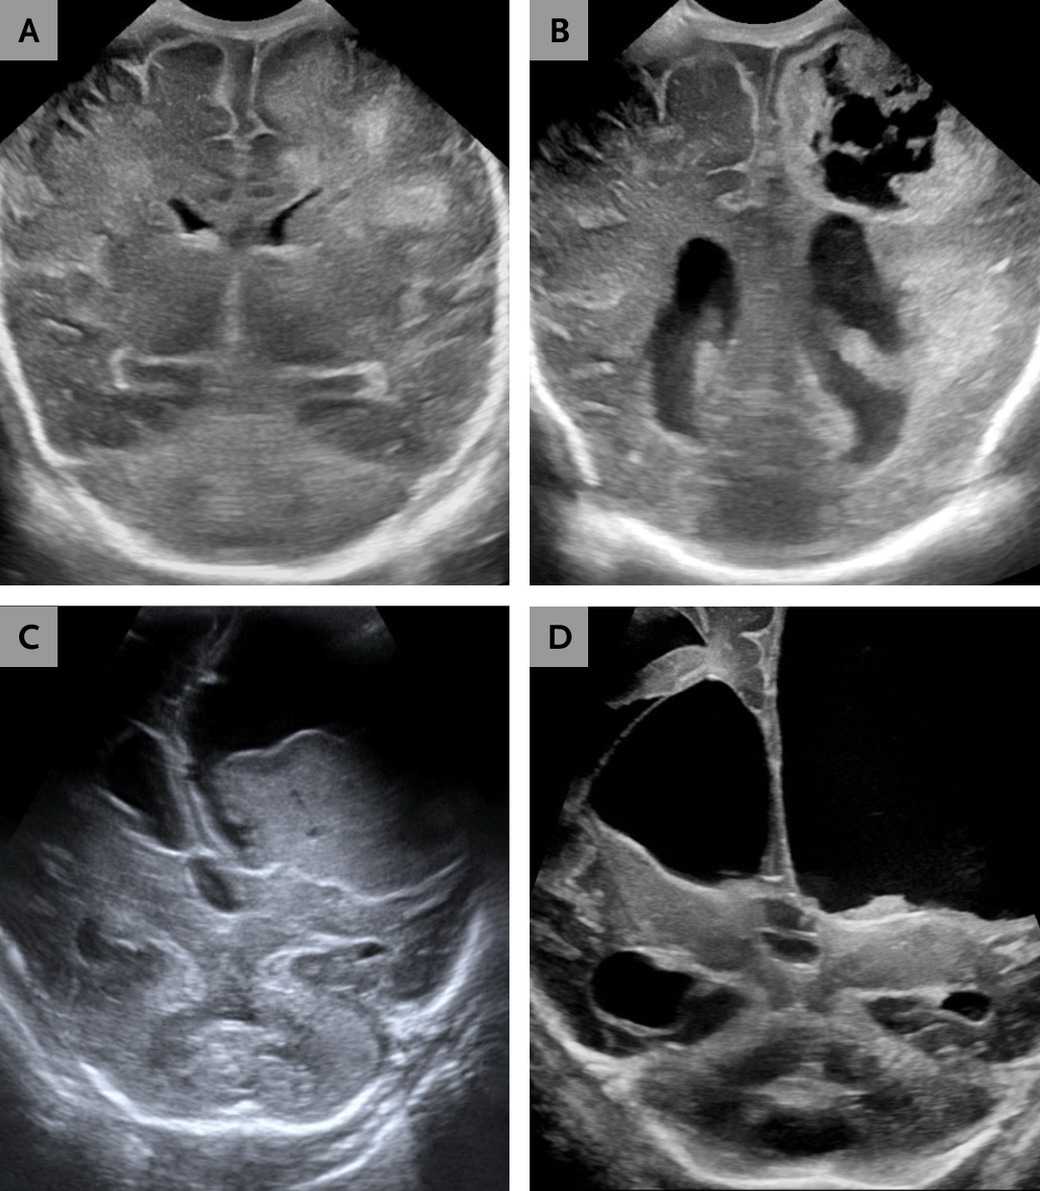

В одном из случаев речь шла о двухмесячной недоношенной девочке, родившейся на 26-й неделе беременности. Из-за дыхательной недостаточности и судорог ей провели посев крови, который выявил грамотрицательные палочки. В крови и спинномозговой жидкости обнаружили Paenibacillus thiaminolyticus, других патогенов выявлено не было. На УЗИ (для младенцев это распространенный, быстрый и дешевый способ нейровизуализации) проявились прогрессирующая гидроцефалия (расширение желудочков мозга), энцефаломаляция (связанное с воспалением размягчение вещества мозга) и образование абсцесса (гнойника), что потребовало установки шунта.

Второму младенцу диагноз поставили на 37-й день после преждевременных родов на 33-й неделе беременности. Поводом для госпитализации послужили плохой аппетит и отсутствие реакции на внешние раздражители. В анализах крови и спинномозговой жидкости снова был обнаружен Paenibacillus thiaminolyticus, а при УЗ-визуализации выявили так называемый ликвационный менингоэнцефалит, при котором ткани мозга начинают превращаться в вязкую жидкость.